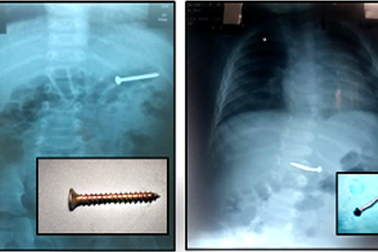

Cha mẹ sơ ý, 2 trẻ nhỏ suýt thủng ruột vì nuốt đinhNhập viện sau nhiều ngày quấy khóc, bỏ bú các bệnh nhi được bác sĩ kiểm tra hình ảnh thì phát hiện trong đường tiêu hóa có dị vật cản quan. Qua phẫu thuật nội soi, bác sĩ đã gắp được những cây đinh khi vừa trôi qua dạ dày giúp các bé tránh nguy cơ thủng ruột.

Bé trai 6 tuổi nuốt ốc vít sắt vào ổ bụngNuốt phải chiếc ốc vít sắt vào trong bụng, cháu bé 6 tuổi không có biểu hiện đau bụng, buồn nôn hay khó thở, các dấu hiệu sinh tồn đều ổn định.